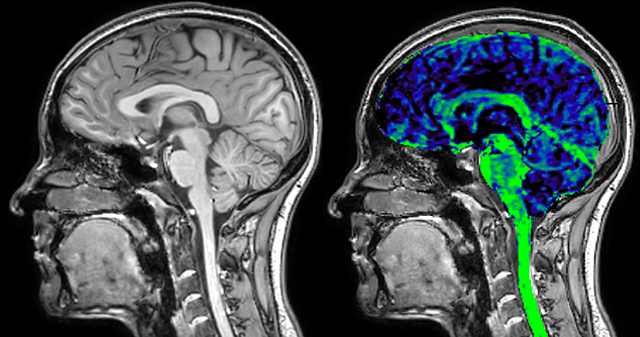

T1 - Weighted, Myelin Water Fraction Superimposed

MWI Spinal cord coverage

Spinal cord coverage

MWI Smaller, more isotropic voxels

Smaller, more isotropic voxels

MWI Excellent detail in quantitative maps

Excellent detail in quantitative maps

Images courtesy of Adam Dvorak, Department of Physics and Astronomy, University of British Columbia

20%

Myelin water fraction

0%

Dr. Rauscher says, “For MWI we perform 3D T2 with 32 or more echoes. This used to take a long time, but with Compressed SENSE we can decrease this to ten minutes for the whole head. Because of the large field of view (FOV) on the readout direction, we even get information from the brainstem, which we previously missed when we were using the GRASE approach. Having the whole head scan is nice because it has spatial resolution, orientation and FOV that are comparable to the standard 3D clinical MS scans, including the FLAIR and 3D T2, and a 3D T1 for brain volume.”